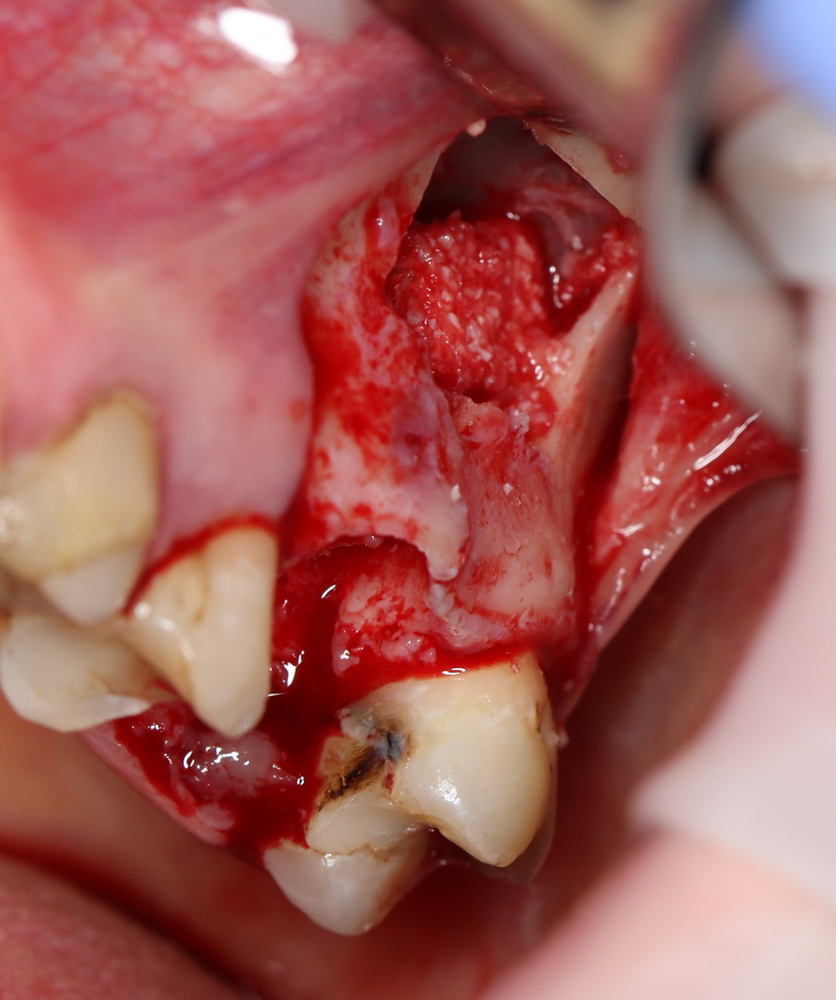

Необходимым условием для проведения этого вмешательства является стадия ремиссии воспалительного процесса в области удаляемого зуба, отсутствие или небольшие размеры очагов хронического воспаления в прикорневой зоне (рис 49, 50, 51):

Рисунок 49, 50, 51. Проведение операции синуслифтинга одномоментно с удалением зуба: слева – скелетирование стенки верхней челюсти, подготовка к удалению зуба, в центре – лунка удаленного зуба (виден небольшой очаг деструкции костной ткани вследствие хронического периодонтита), справа – заполнение субантральной полости спейсером.

К установке имплантов можно приступать через 3-4 месяца (рис 52, 53):

Рисунок 52, 53. Установка импланта через 3 месяца после удаления зуба и синуслифтинга: слева – скелетирование верхней челюсти, справа – установленный имплантат.